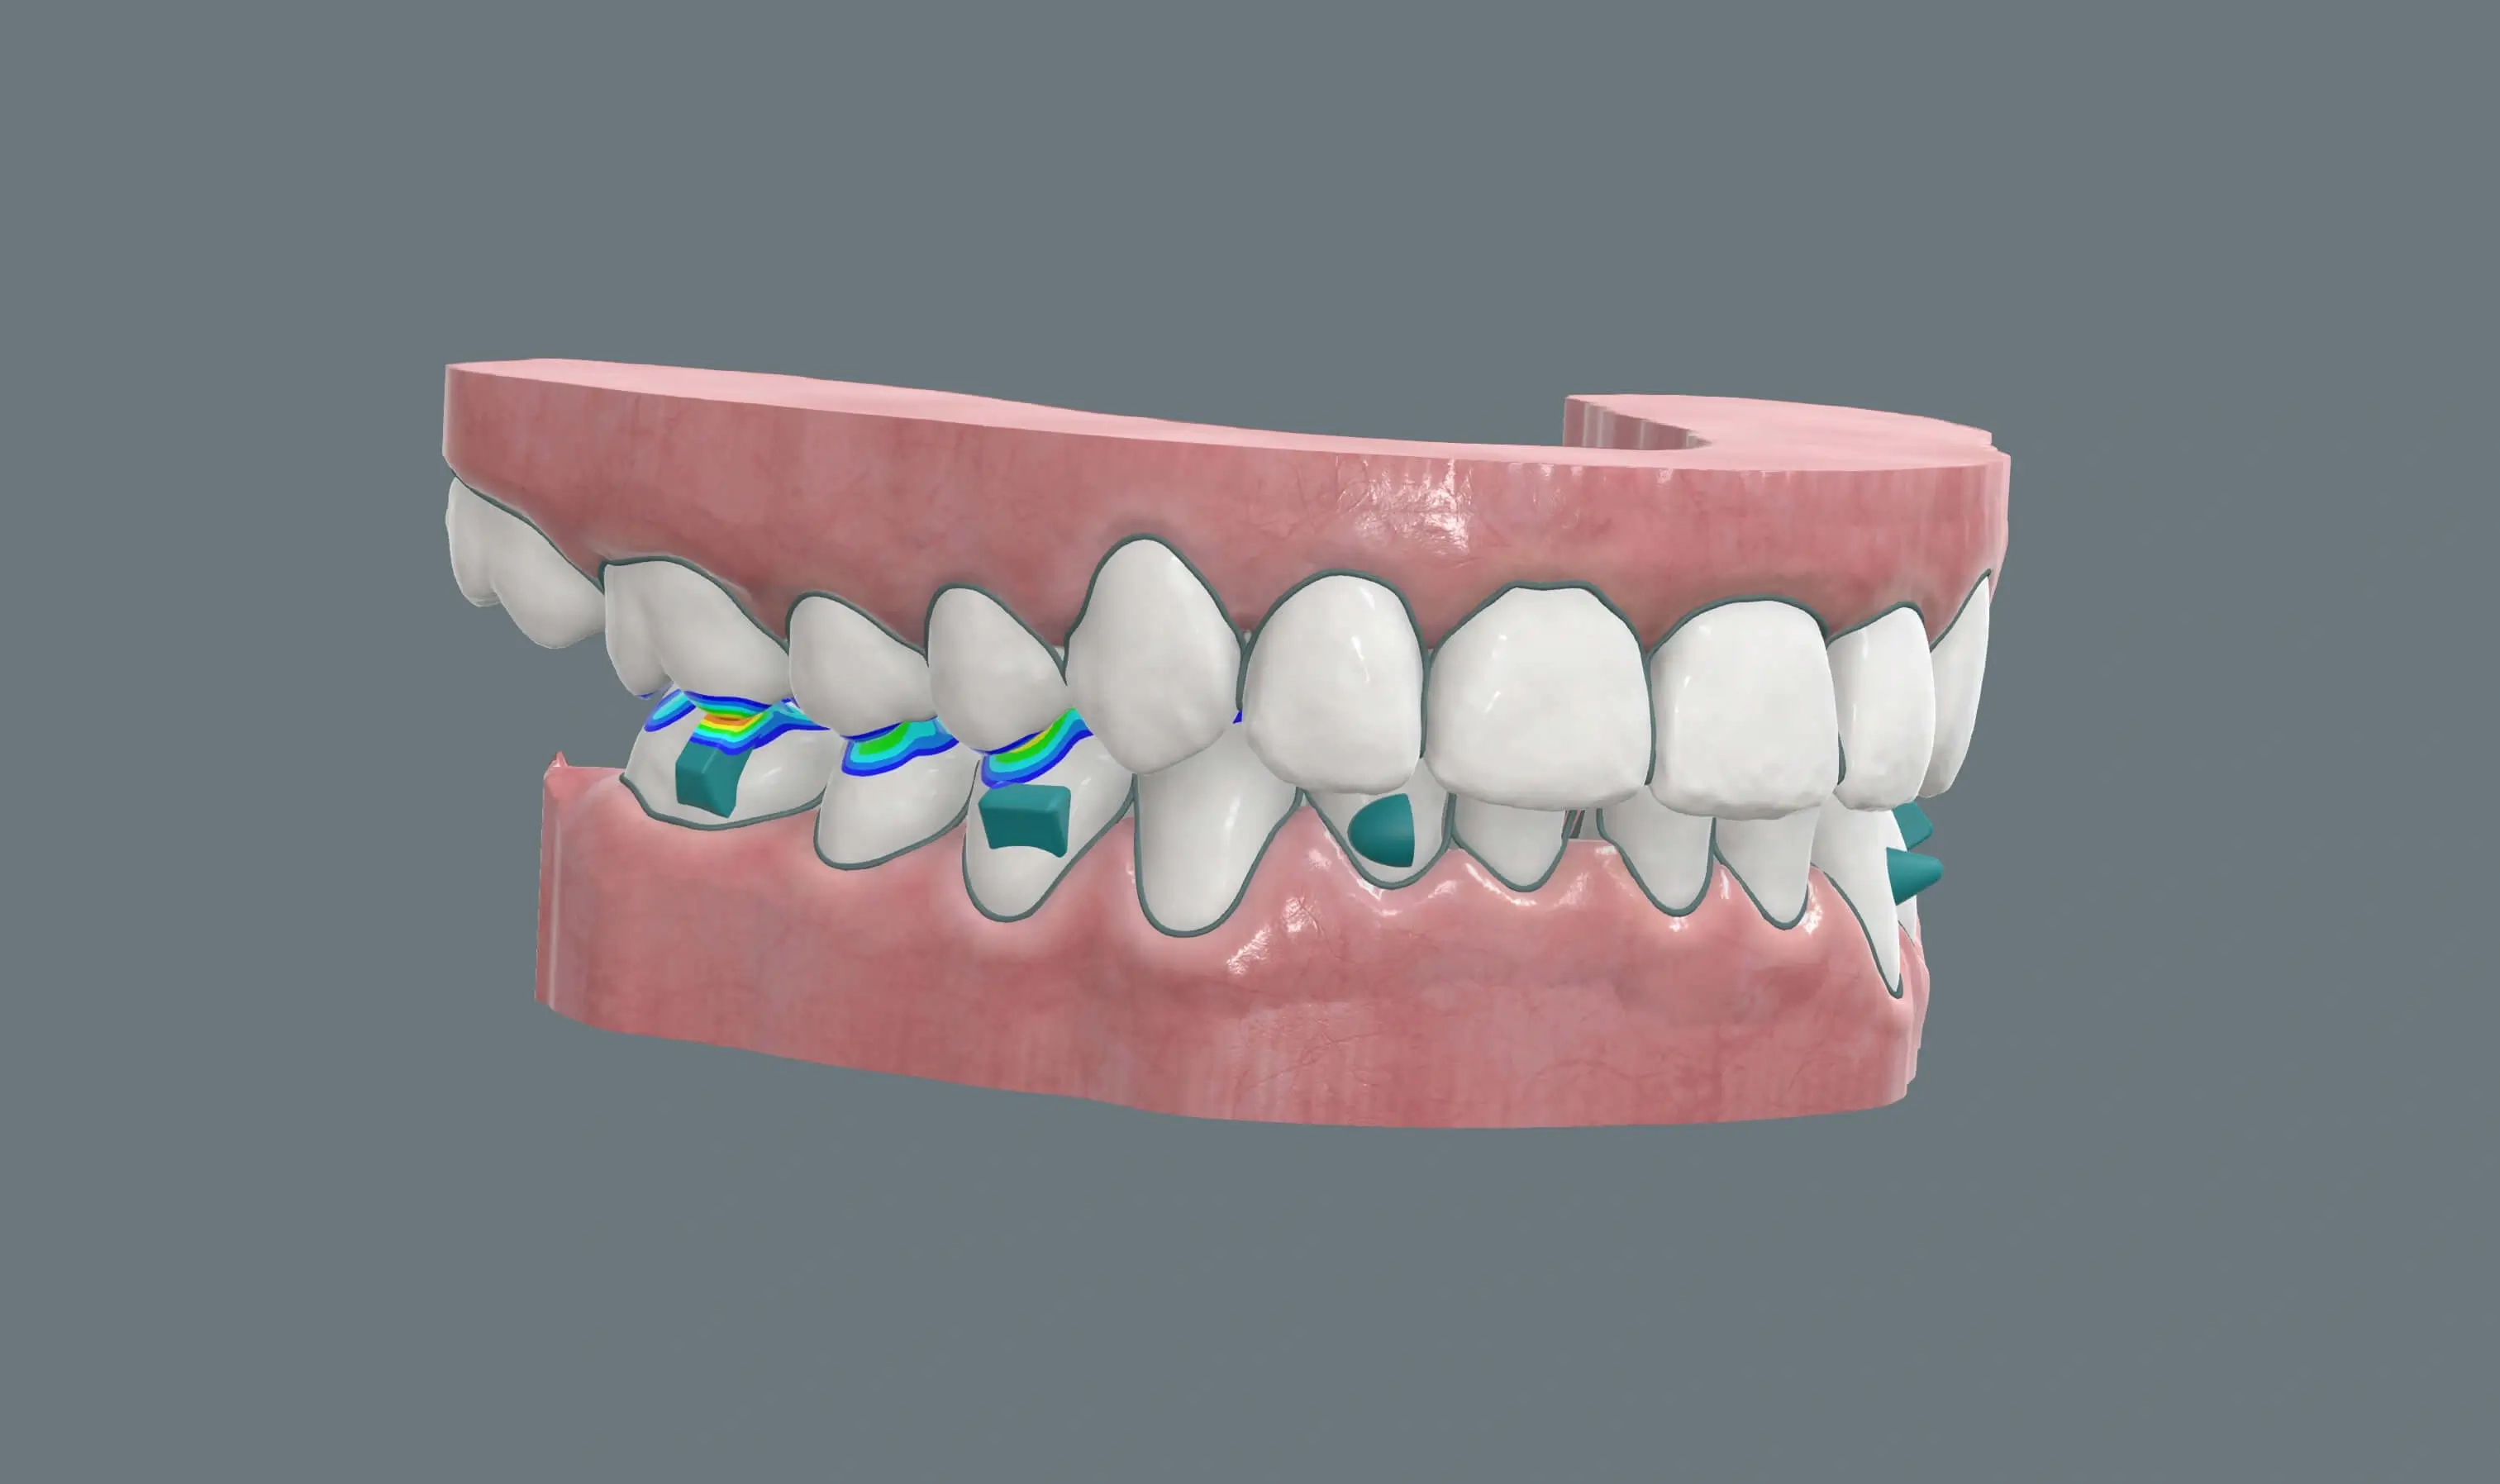

Абсолютный контроль над каждым миллиметром движения зубов и суставов — точная диагностика и уверенное планирование в мире элайнеров.

Планирование ортодонтического лечения под любые междисциплинарные задачи.

Производственная точность кап составляет не более 0,1 мм, благодаря чему они плотно прилегают к зубам и позволяют точнее прогнозировать результат. Однако клиническая точность зависит не только от производства. Она определяется реалистичностью плана лечения врача - от этого будет зависеть качество сетапа, выбор механики (например, аттачментов или тяг). Также важное значение имеют соблю�дением режима ношения и регулярной проверкой посадки кап на приемах.

Система FlexiLigner подходит для лечения разной степени деформации — от легкого выравнивания до комплексной коррекции прикуса и работы с височно-нижнечелюстным суставом. Если говорить о доказательной базе, ключевым фактором является не сам диагноз, а грамотный отбор случая и соблюдение протокола. В лёгких и средних случаях результат сопоставим с брекетами, а в сложных ситуациях часто требуется усиленная механика и жесткий контроль результата.